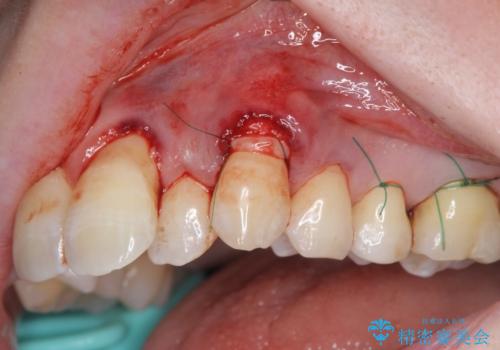

プラークコントロールが十分に行えるようになったのち、結合組織移植を用いた根面被覆手術を行います。

手術は静脈内麻酔下で行いほとんど記憶もない状態で終えることができます。

- 外科手術のため、術後に出血、痛みや腫れ、違和感を伴います

- 口腔内の状態によっては適応できないことがあります